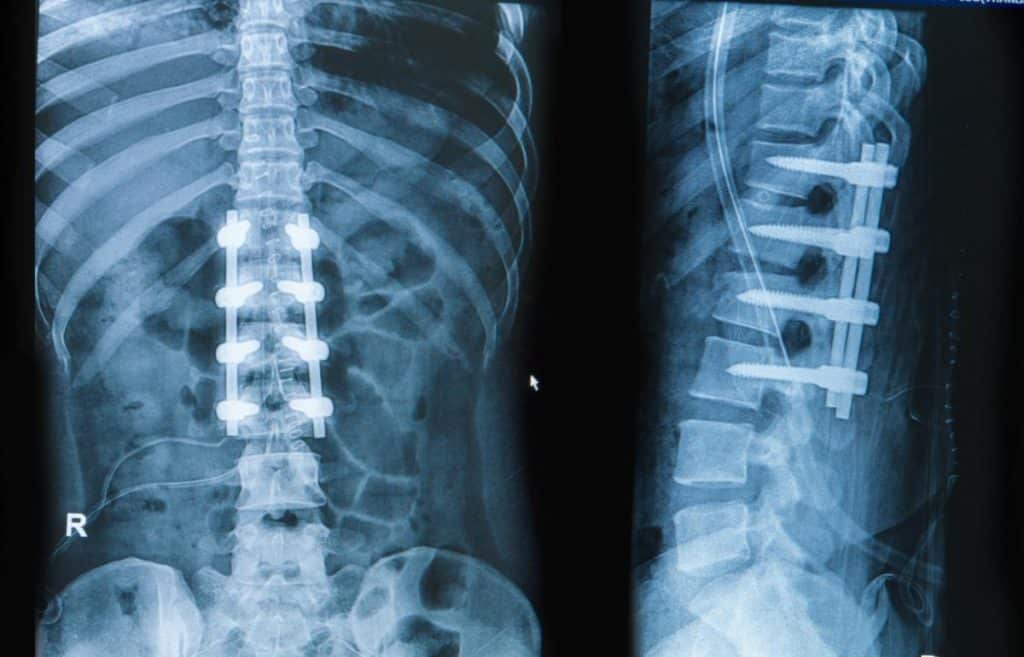

Can spinal fusion surgery be avoided?

Marc Darrow, MD, JD. In our practice we often see patients who are in severe back pain. Many have already been recommended to some type of fusion surgery. Their fusion surgery recommendation may be based on pain and it may be based on an MRI image that while showing degenerative changes in the spine, may … Continue reading Can spinal fusion surgery be avoided?